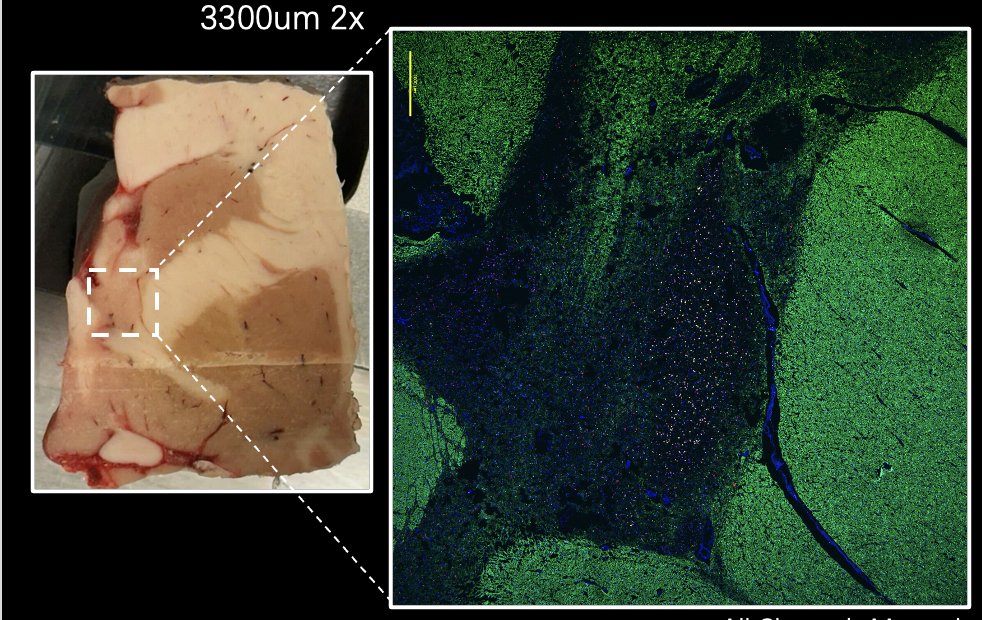

Some human brain too for #FluorescenceFriday. Painstaking work from RA Yufeng Du and @SvitlanaBach to characterize the molecular neuroanatomy of this not well characterized area of the human brain